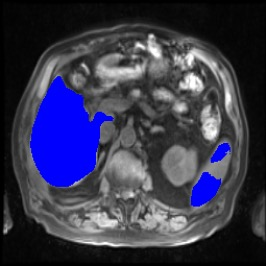

Integrating high-level semantically correlated contents and low-level anatomical features is of central importance in medical image segmentation. Towards this end, recent deep learning-based medical segmentation methods have shown great promise in better modeling such information. However, convolution operators for medical segmentation typically operate on regular grids, which inherently blur the high-frequency regions, i.e., boundary regions. In this work, we propose MORSE, a generic implicit neural rendering framework designed at an anatomical level to assist learning in medical image segmentation. Our method is motivated by the fact that implicit neural representation has been shown to be more effective in fitting complex signals and solving computer graphics problems than discrete grid-based representation. The core of our approach is to formulate medical image segmentation as a rendering problem in an end-to-end manner. Specifically, we continuously align the coarse segmentation prediction with the ambiguous coordinate-based point representations and aggregate these features to adaptively refine the boundary region. To parallelly optimize multi-scale pixel-level features, we leverage the idea from Mixture-of-Expert (MoE) to design and train our MORSE with a stochastic gating mechanism. Our experiments demonstrate that MORSE can work well with different medical segmentation backbones, consistently achieving competitive performance improvements in both 2D and 3D supervised medical segmentation methods. We also theoretically analyze the superiority of MORSE.